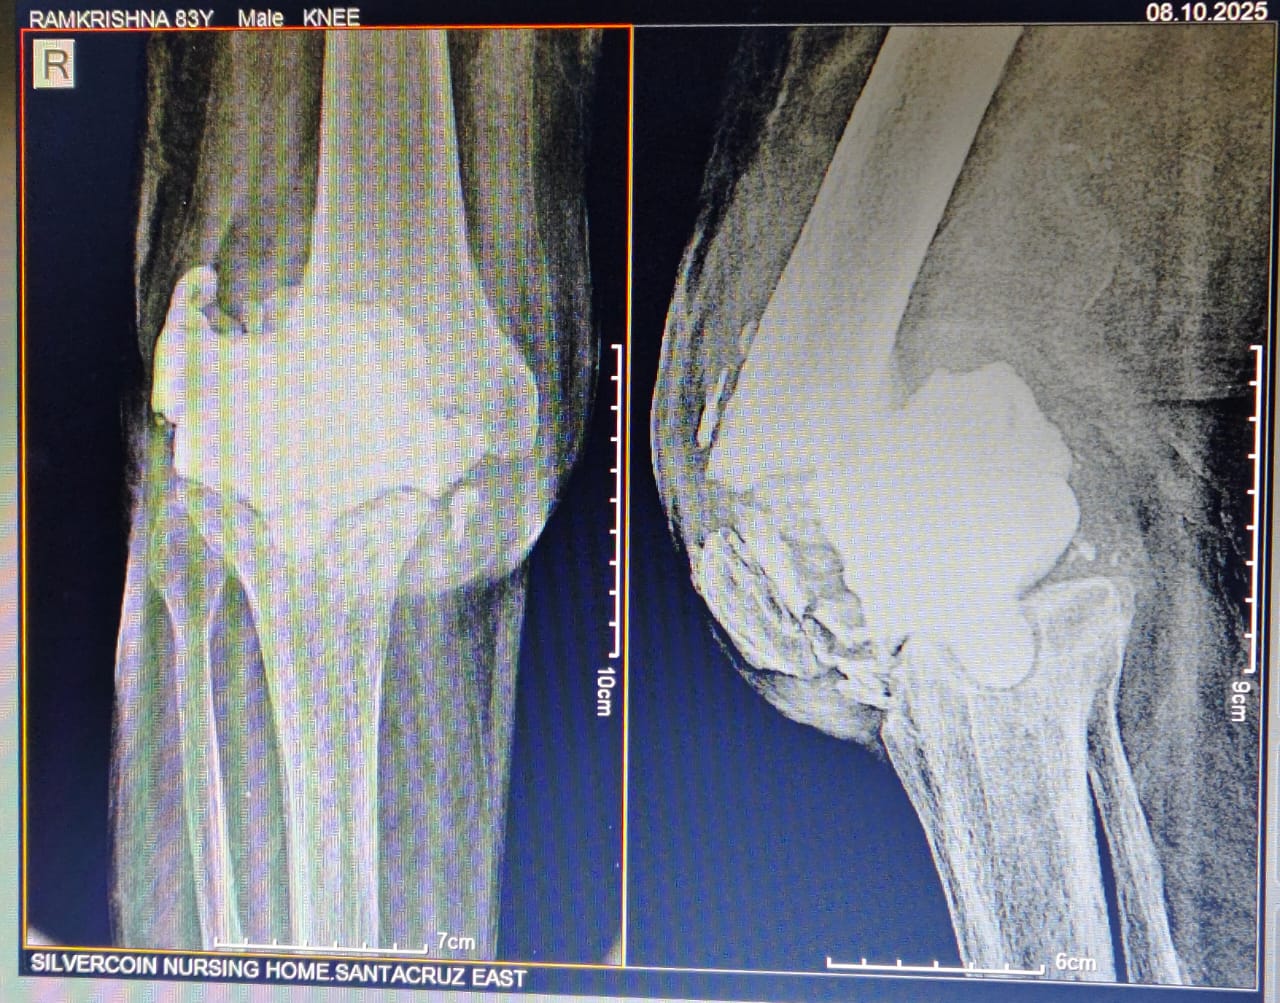

Dr Ajay Randive : IS MS Ortho (Mumbai) MRCSI ( UK) Consultant knee, Hip ,& Spine Surgeon, Dr Ajay Randhive is a eminent Knee, Hip , & Spine Surgeon practicing in to areas Andheri East,Santacruz East. Dr Ajay Randive did his MS Ortho residency from LTMMC, Sion Hospital Mumbai. He did overseas training in UK from 2003 till 2008. He is trained in total Knee Replacement, Hip Replacement, Revision Hip Replacement And Revision Knee Replacement Surgeries. He has worked at The Royal London Hospital. IN London where he worked a clinical fellow in joint Replacement unit. He has carried out more than 5000 Knee Replacement surgeries, 2500 Hip Replacement Surgeries, More Than 500 Revison Knee And Hip Replacement Surgeries 600 Spine surgeries & more than 1500 arthroscopic surgeries (Knee & Shoulder).